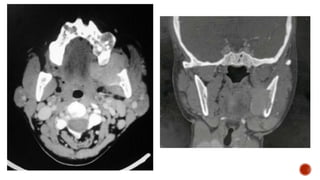

 Benign , locally aggressive tumor

 Origin – Spenopalatine foramen

 C/f – painless progressive unilateral nasal obstruction , epistaxis

 CT – Heterodense mass with avid enhancement , widening of pterygopalatine

fossa, bowing of posterior wall of maxillary sinus (Holman Miller sign), bony

erosion

 Main blood supply – Internal maxillary artery, branch of ECA , others – ascending

pharyngeal , palatine

 Treatment – Preop Embolization – Surgical resection